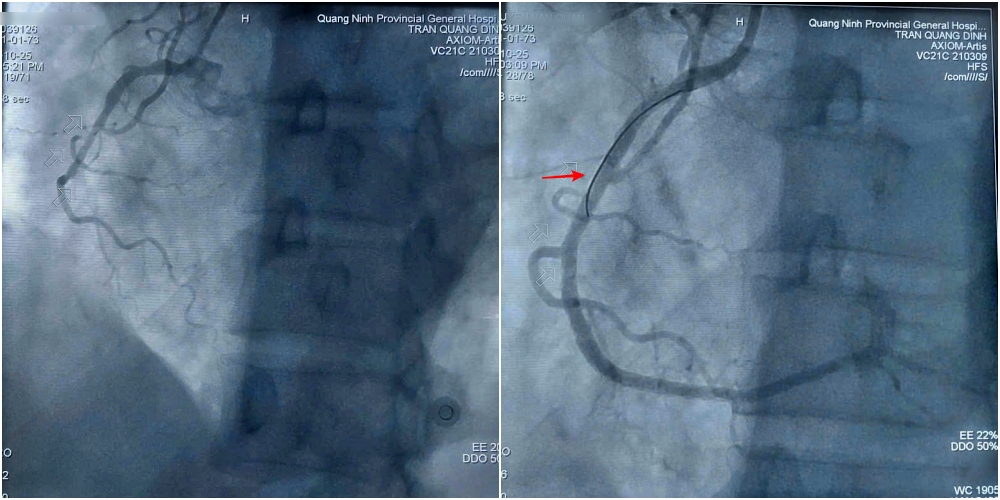

Hình ảnh trước và sau can thiệp đặt stent tái thông mạch vành cho bệnh nhân Q.

Sau khi hội chẩn và giải thích rõ tình trạng cho gia đình, ca can thiệp được đội ngũ bác sĩ khoa Phẫu thuật và Can thiệp Tim mạch tiến hành khẩn trương ngay sau đó. Kết quả chụp mạch cho thấy tổn thương nặng 3 thân động mạch vành, trong đó hẹp tắc hoàn toàn động mạch vành phải. Kíp can thiệp tiến hành nong bóng và đặt 2 stent để tái thông động mạch bị hẹp tắc. Hình ảnh chụp kiểm tra sau thủ thuật cho thấy stent thông tốt, dẫn máu trở lại nuôi tim.